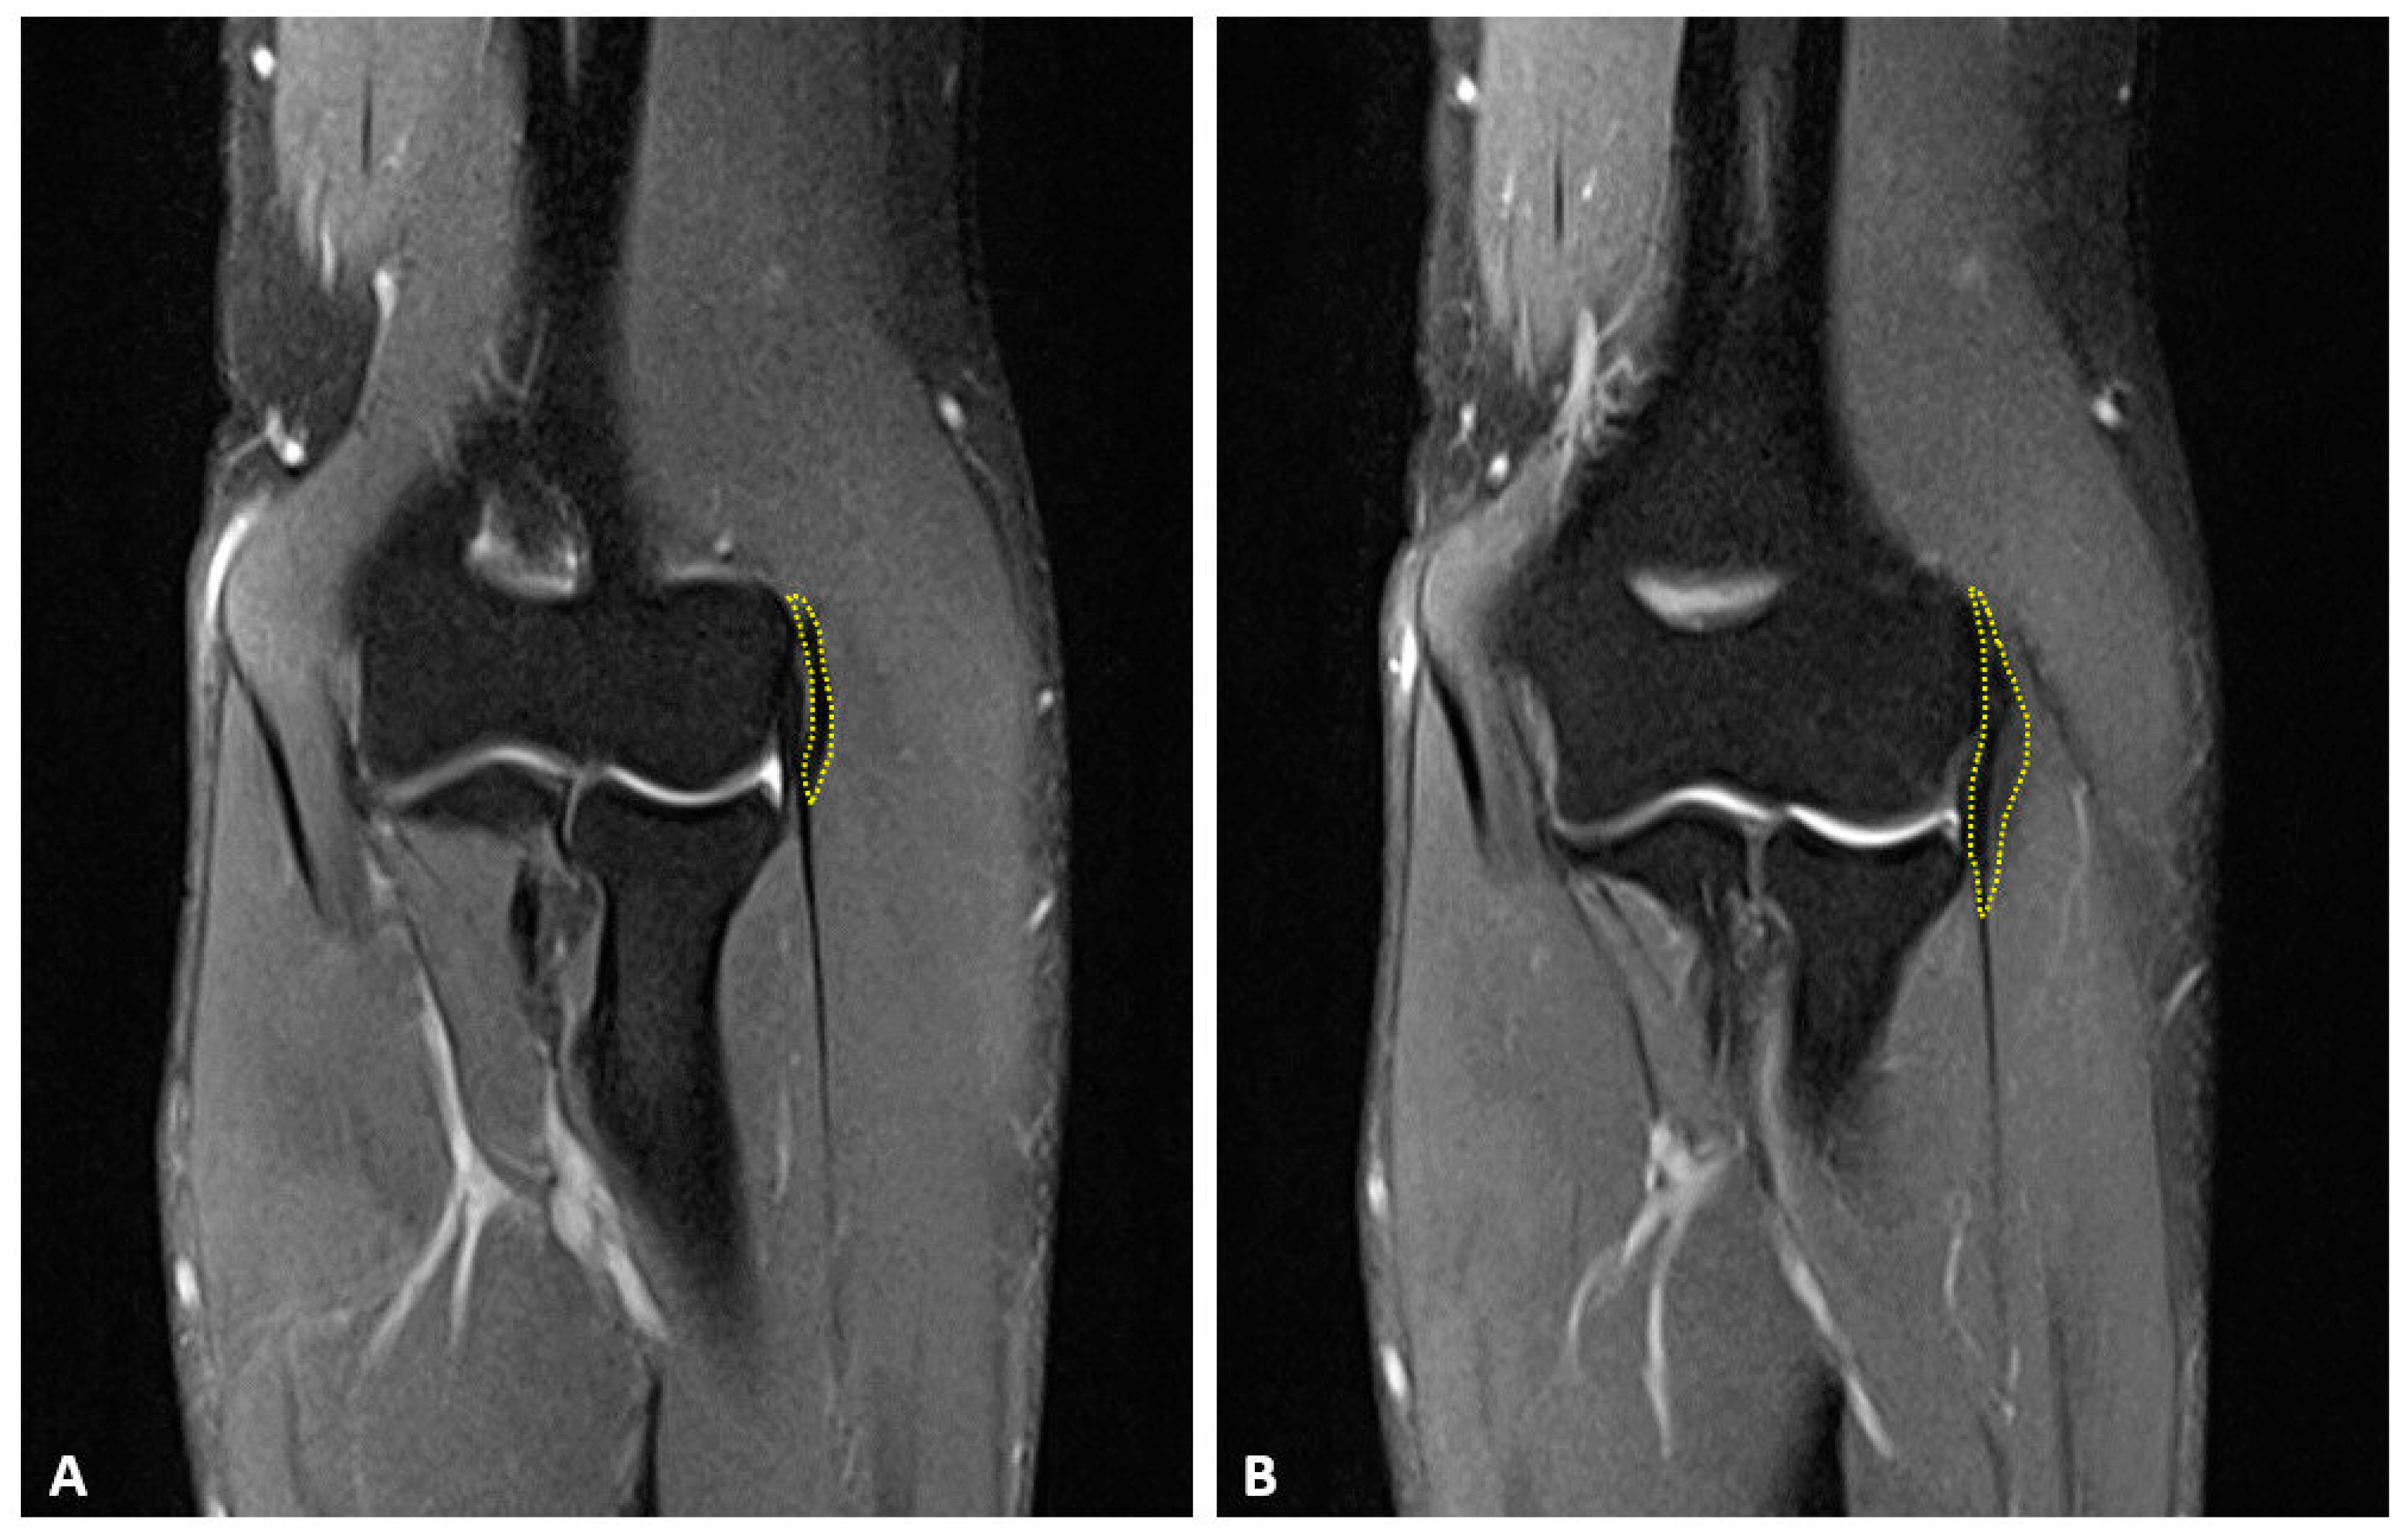

2.2. Surgical Technique